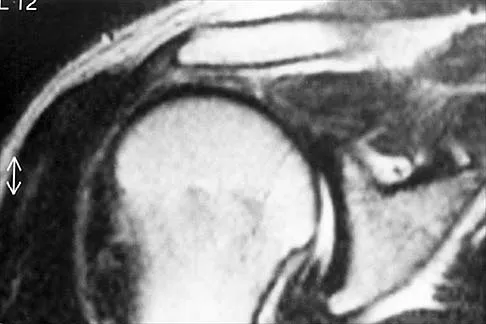

A 14-year-old boy has an asymptomatic mass on the right arm. MRI scans and biopsy specimens are shown in Figures 51a through 51d. Immunostaining is positive for desmin. Additional staging studies should include